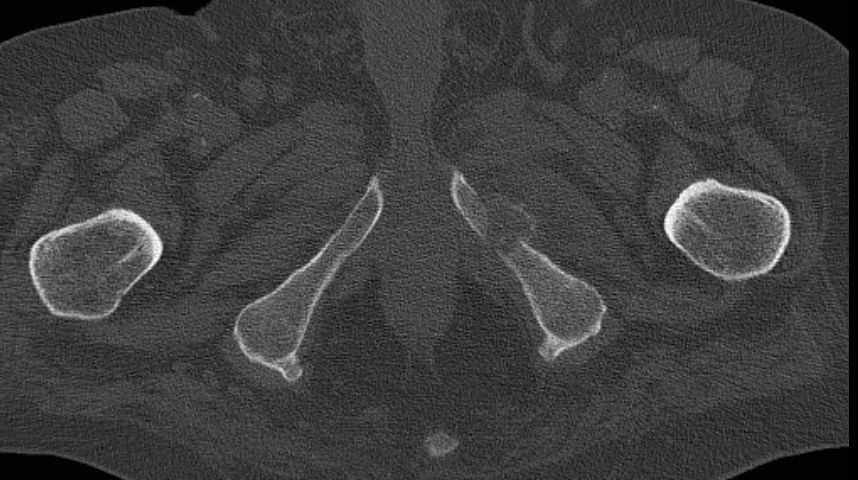

| Knochenmetastasen | 72-jähriger Patient, der vor 3 Jahren ein Harnblasen-Ca hatte: Blasenteilresektion. | Vor 2 Jahren 1. Rezidiv T1 G2: TUR-B. Vor einem Jahr 2. Rezidiv: Blasenteilresektion pT3a G3. | Vor 4 Monaten Lungenmetastastasen. Jetzt Schmerzen beim Sitzen und Belastung des linken Beins. |

Metastase Schambein links mit Kallusbildung.![]() |